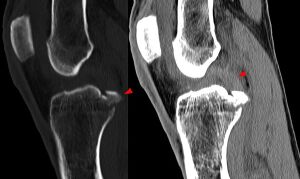

Röntgenbild: Kreuzbandriss - Hellerhoff commons.wikimedia.org, CC BY-SA 3.0